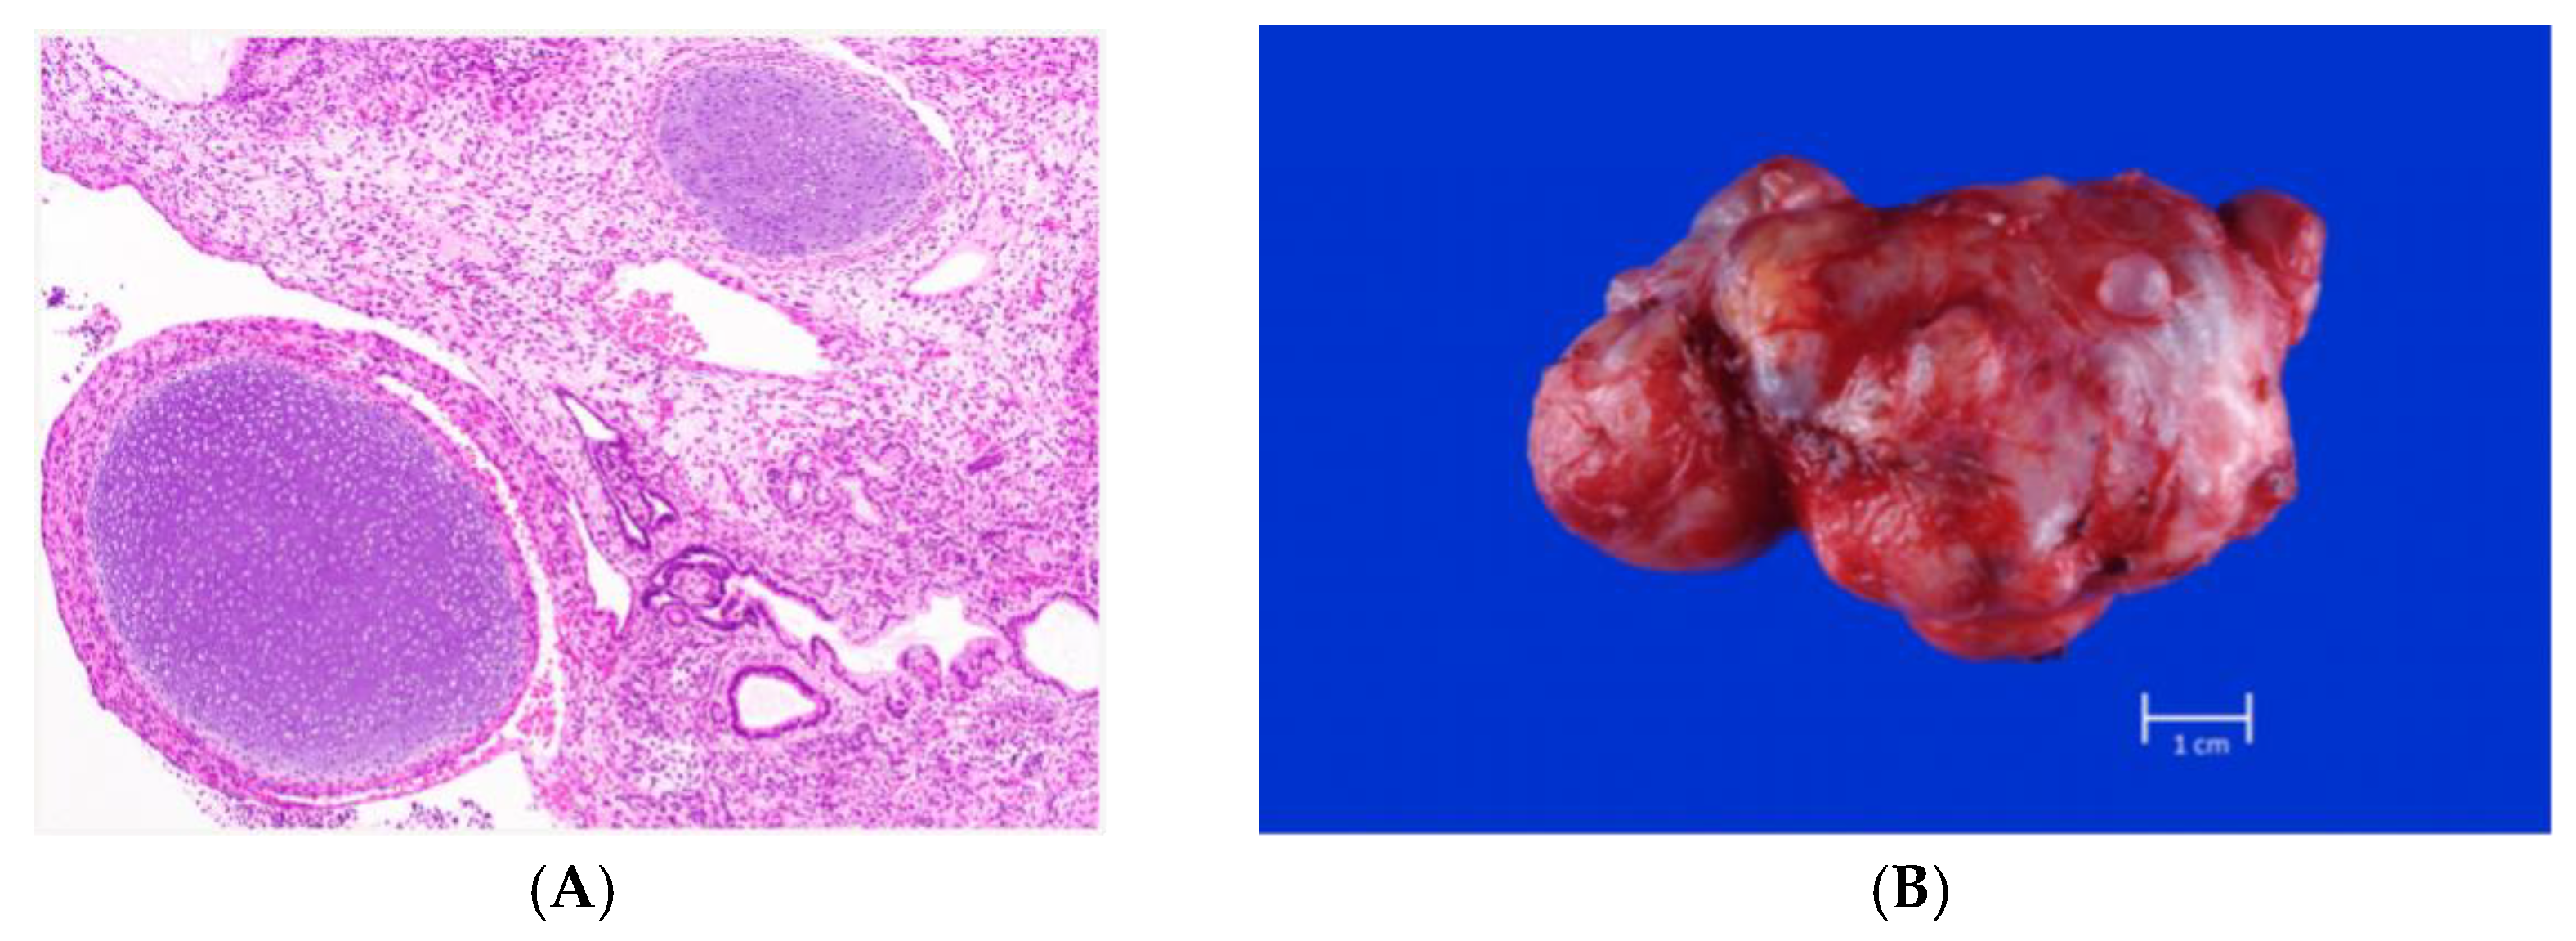

- Varlas, V.N.; Cloțea, E.M.; Varlas, R.G.; Pop, A.; Peneș, O.; Crețoiu, D.; Dima, V.; Bălănescu, L. Immature Sacrococcygeal Teratoma: A Case Report and Extensive Review of the Literature. Diagnostics 2024, 14, 246. [Google Scholar] [CrossRef] [PubMed]